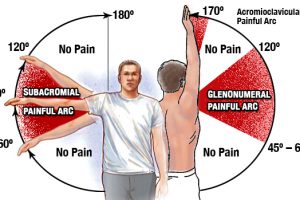

この症状をお持ちの方の特徴として、バンザイをした時に腕が真上まで挙げられなかったり、挙がったとしても腰を反らせてしまう代償運動を行ってしまいます。

肩甲骨が前に傾くと、肩が本来のポジションでなくなってしまうので、きちんとバンザイの動作ができなくなってしまいます。

この状態で運動を続けていくとどんどん痛みが出やすい体になるのと、小胸筋の間を通っている神経や血管を圧迫してしまいます。